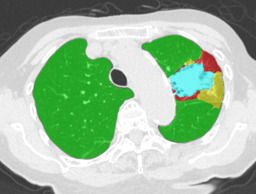

Recall, precision, and dice coefficient (a.k.a F-measure) were used for the evaluation. For the sake of the evaluation, continuous softmax outputs were converted into discrete class labels by selecting the classes that gave the maximum probability. Table 2 shows the evaluated metrics for each method. By paired t-tests, statistically significant differences were confirmed between the proposed method (λ=0.1𝜆0.1\lambda=0.1) and other methods in dice coefficients. As shown in Table 2, utilizing weakly annotated pixels increased precision and λ=0.1𝜆0.1\lambda=0.1 was the optimal value that balances recall and precision in this experiment. Evaluated dice coefficients for the proposed method (λ=0.1𝜆0.1\lambda=0.1) are shown in Figure 2. As shown in Figure 2, even though the proposed method improved the segmentation accuracy, segmentation accuracy varies between slices. Figure 3 shows the confusion matrix of the pixel-wise classification result. In Figure 3, Lweaksubscript𝐿𝑤𝑒𝑎𝑘L_{weak} pixels misclassified as corresponding Lstrongsubscript𝐿𝑠𝑡𝑟𝑜𝑛𝑔L_{strong} (e.g. pixels of lCON¯subscript𝑙¯𝐶𝑂𝑁l_{\overline{CON}} classified as lCONsubscript𝑙𝐶𝑂𝑁l_{CON}) are represented as “Others”. As shown in Figure 3, DLD class combinations with similar texture patterns such as HCM and EMP were misclassified into each other. Figure 4 shows the average result for each DLD class and tested method.

Ground truth Supervised only Proposed (λ=0.1𝜆0.1\lambda=0.1) Proposed (λ=1𝜆1\lambda=1)

CON \blacksquare

Refer to caption Refer to caption Refer to caption Refer to caption

0.839 0.868 0.824

GGO \blacksquare

0.693 0.676 0.876

HCM \blacksquare

0.581 0.770 0.435

EMP \blacksquare

0.793 0.847 0.815

NOR \blacksquare

0.978 0.968 0.974

Figure 4: Average results and dice coefficients for each DLD pattern. Automated segmentation results are superimposed with colors. For each DLD pattern, the slice that gave the median dice coefficient for the proposed method with λ=0.1𝜆0.1\lambda=0.1 was chosen to represent the average result. Note that although CNN performed multi-class segmentation, only one DLD pattern per slice was taken into account for the evaluation.